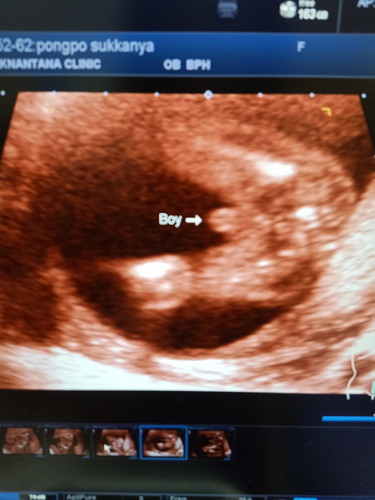

ซาวด์เจอเนื้องอกในมดลูก

ตอนนี้18wค่ะ ได้เพศชาย แต่เจอเนื้องอกในมดลูกด้วย อยากทราบว่าจะแม่ๆท่านไหนที่เคยเป็นบ้างค่ะ